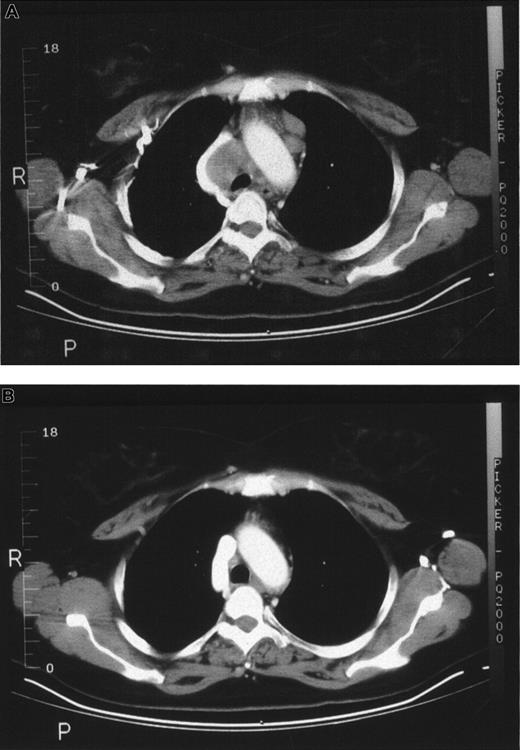

Four patients achieved a complete remission (CR) of their cancer. One patient achieved CR with transient 5% donor chimerism, and the other 3 patients who achieved CR had 100% donor chimerism. The first patient achieved a CR although she had only transient 5% donor chimerism. This patient, a 51-year-old woman with large cell lymphoma, had a relapse after autologous transplantation. Histology at the time of relapse was a follicular mixed lymphoma. She had been treated with radiotherapy and salvage chemotherapy without response. At the time of treatment, she had extensive pretracheal, subcarinal, and hilar adenopathy. Her course is outlined in Table 4. She developed 5% donor chimerism at 1 week after transplantation. Subsequent chimerism studies performed weekly through 4 weeks, at 8 weeks, and every 6 months have shown only recipient cells. There was depression of blood counts, which had increased by the week 8 evaluation. Figure1 demonstrates serial CT images before treatment and at 8 weeks after treatment. The CT scans show a dramatic resolution of the chest adenopathy. The patient is alive and well, 42 months after transplantation. Restaging CT scans at 36 months also showed no evidence of disease and the patient's blood showed all recipient cells.

CT scans from patient 1.

(A) Chest CT scan images before treatment. (B) Chest CT scan images at 8 weeks after treatment shows resolution of adenopathy.